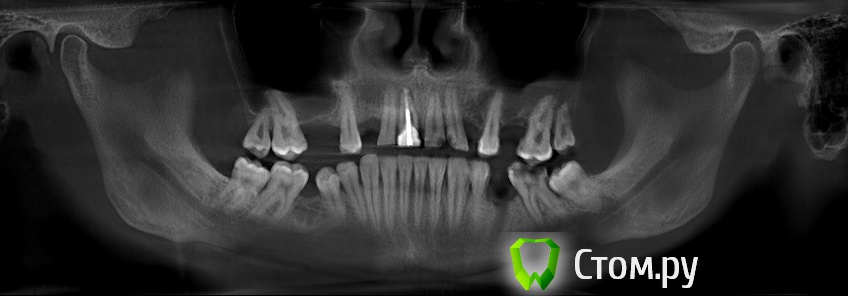

sergey765 Опубликовано 11 июня, 2014 Автор Поделиться Опубликовано 11 июня, 2014 посмотрите пожалуйста КТ. Ссылка на комментарий

sergey765 Опубликовано 11 июня, 2014 Автор Поделиться Опубликовано 11 июня, 2014 могу вам ещё снимков выложить.их довига. беспокаят меня боли после удаления .прошло 5 недель. снимки девушка лет 20 эти смотрела. сказала что у меня там инфекции дофига. типа давай я тебя на понедельник к хирургу запишу. он ранку вскроет. прочистит Ссылка на комментарий

Bier Опубликовано 11 июня, 2014 Поделиться Опубликовано 11 июня, 2014 это все не информативные кадры, в прикрепленных темах есть инструкция, выкладывайте КТ целиком, наш рентгенолог скачает и выложит срезы. 3 Ссылка на комментарий

sergey765 Опубликовано 12 июня, 2014 Автор Поделиться Опубликовано 12 июня, 2014 (изменено) ещё хочу добавить. когда у меня удаляли 5 недель назад мой зуб. из лунки выскочил какой-то кусок черного мяса размером почти с горошину. это не кровяной сгусток а именно кусок застывшиго черного мяса. крови почти не было. так во этот кусок мяса залез обратно в десну-челюсть только дня через 4. и видна в лунке была только челюсть желтого цвета и посередине дырка из кости куда этот кусок мяса залез. потом я пришел к врачу который удалял она мне на кость положила лекарство желтого цвета которое тупо застыло и не растворялось. стало как камень. от запаха этого лекарства я реально чуть не сдох. так было ещё дней 5. потом лунка затянулась но кусок желтой кости торчит досихпор. еще при удалении пол левой челюсти побелело. образовался какой-то белый налет на левой половине верхней и нижней десне. через 2-3 дня после удаления я провел пальцем по деснам и этот налет с десны снялся но остался белый комок на пальце которым я проводил по десне... еще у меня постоянно уже года 2 наверно из левого глаза идет временами гной... посмотрите на снимке там даже с левой стороны челюсти (правой снимка) есть какое-то черное пятно. Изменено 12 июня, 2014 пользователем sergey765 Ссылка на комментарий

sergey765 Опубликовано 12 июня, 2014 Автор Поделиться Опубликовано 12 июня, 2014 (изменено) и ещё. удаление было левая сторона нижней челюсти 3-й зуб... 2-й весь страшный вот в нём дофига инфекции. из-под десны там камень или гной идет фиг его знает. а в самом зубе какая-то белая фигня. ну его сказали можно типа вылечить. сейчас короче загружаю файл КТ. размер 310мб Изменено 12 июня, 2014 пользователем sergey765 Ссылка на комментарий